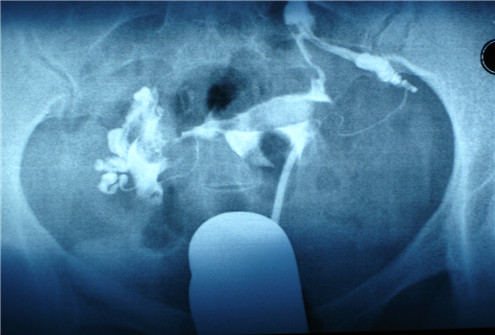

2.找节育环

然后医生用探针探测宫腔深度,再在宫腔四周寻找节育环的放置部位。

3.取节育环

最后,医生找到了节育环之后,夹住它,左右转动,使之慢慢剥离附着部位。